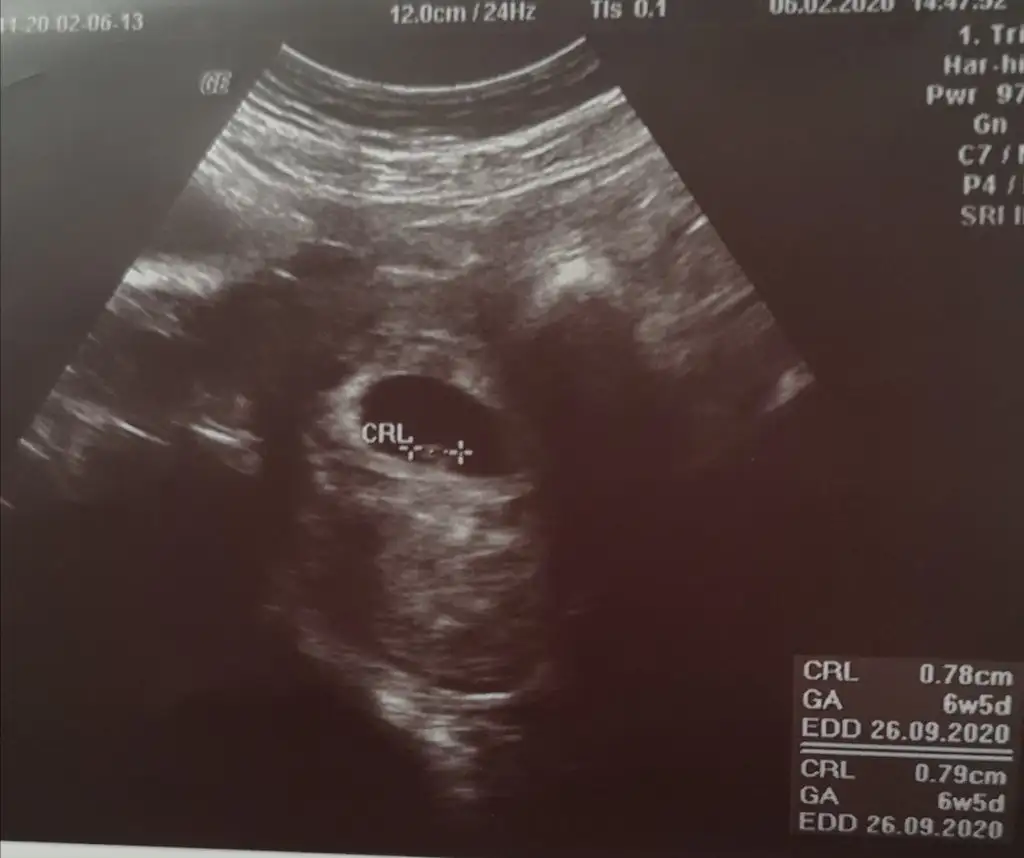

Ramzi teorisi

6-7 . haftalara ait ultrason görüntünüz eliniz de varsa inceleyin. Bebek sağ tarafta ya da sağ tarafa daha yakınsa kız , Eğer bebek sol tarafta ya da sol tarafa yakınsa cinsiyeti erkektir.